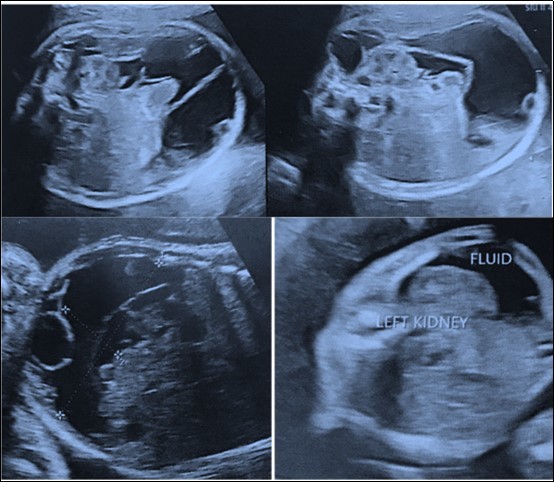

34 year old G2P1001 was referred to our institute at 21weeks period of gestation for a fetal abdominal cystic mass for further evaluation and management. At referral, she had an anomaly scan reporting a left sided retroperitoneal collection of 3x2 centimeters with septations surrounding the kidney and extending up to left pelvis suggestive of lymphocoele in the fetus. In second trimester anomaly scan nuchal fold thickness was normal, there were no markers suggestive of aneuploidy and no other malformation was seen. In follow-up scans, there was increase in size of the collection upto 8x6 cm at term which also shown a subcutaneous component of around 5x4 cm along the left fetal torso in the lumbar region (Figure 2a). Growth parameters were normal and amniotic fluid was adequate. She was hypothyroid on treatment and developed gestational diabetes at 32weeks period of gestation which was managed with medical nutrition therapy. Her first child was born by cesarean section and had no congenital malformation. Index pregnancy was terminated by an elective cesarean section at term as she was not willing for vaginal birth after caesarean. Male baby of 3.4kg was born with good apgar score. He had a left sided lumbar cystic swelling of 5x6cm, reducible inguinal hernia and undescended testes on the left side. Postnatal echocardiography was normal and postnatal USG shown similar features of the cyst. Baby was active, euthermic, euglycemic, passed urine and stool and was well accepting feeds hence discharged at day 3 of life. He was conservatively followed and at 6 months postnatal visit, size of the lumbar swelling was clinically decreased in size and infant had age appropriate milestones. Ultrasonography (Figure 2b) and CECT scan at one year of age was suggestive of large cystic lesion in the abdomen and pelvis (13*6*12 cm) with extension into postero lateral subcutaneous planes of abdominal wall through a defect in the left oblique muscle. Rest of the abdominal organs and large vessels were normal and there was no ascites or lymphadenopathy. However child is doing well at one year of age without any clinical obvious increase in the size of lumbar swelling.

Figure 2a.Images of Ultrasonography at second trimester of pregnancy